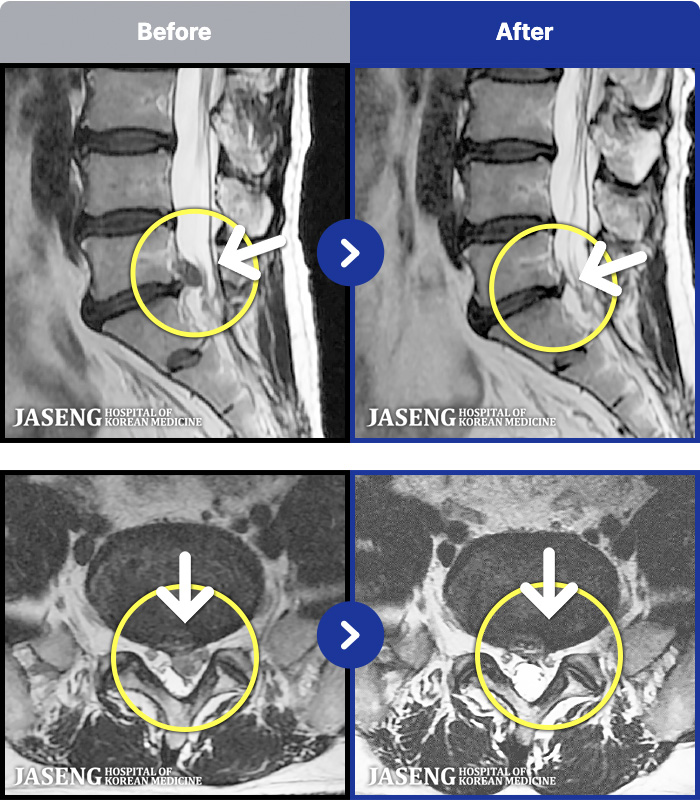

MRI ġ

1,301 MRI ũ ʸ Ȯϼ.